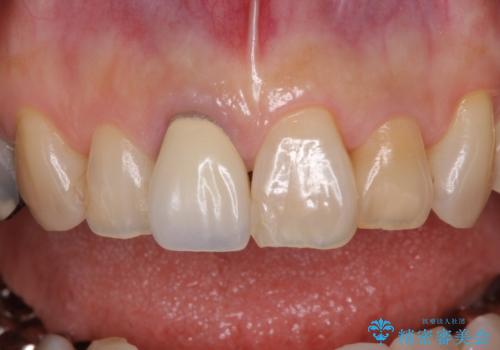

前歯は神経を取り除いて変色した歯や金属の縁が見える歯などがあり審美的に気になっていましたが、治療するかどうかは悩んでいらっしゃいました。

ところが、奥歯の治療を開始する前に、神経が失活して根尖部に病変のある前歯が著しく痛み出したため、根管治療を行うこととなりました。

奥歯の治療をしている間に前歯の治療をどのように勧めるのか検討していただき、最終的には4歯を一度に治療し、審美的に仕上げることとしました。